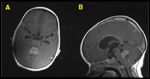

FIGURE 8

Choroid Plexus Tumors

The histologic findings in a choroid plexus papilloma includes a papillomatous component lined by a single layer of columnar or cuboidal epithelium and a central core of vascular stromal tissue, and the absence of mitosis and normal tissue invasion. In contrast, choroid plexus carcinoma consists of sheets of cells without papillary forma-tion, nuclear atypia and pleomorphism, frequent mitoses, and invasion of subependymal brain tissue. Children with choroid plexus tumors frequently present with hydrocephalus due to mechanical obstruction and/or CSF overproduction (Figure 8).[81] Up to 30% of children present with metastatic disease at diagnosis.